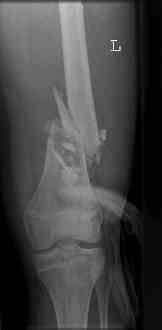

16 yr old boy, high energy motorcycle trauma trauma in July 2005 with:

- hip dislocation + acetabular fracture L

- distal femoral fracture L

- tibial shaft fracture L

- metatarsal fractures L

July 05

july 05: LISS femur, LCP plate tibia, double recon. plate post. acetabulum